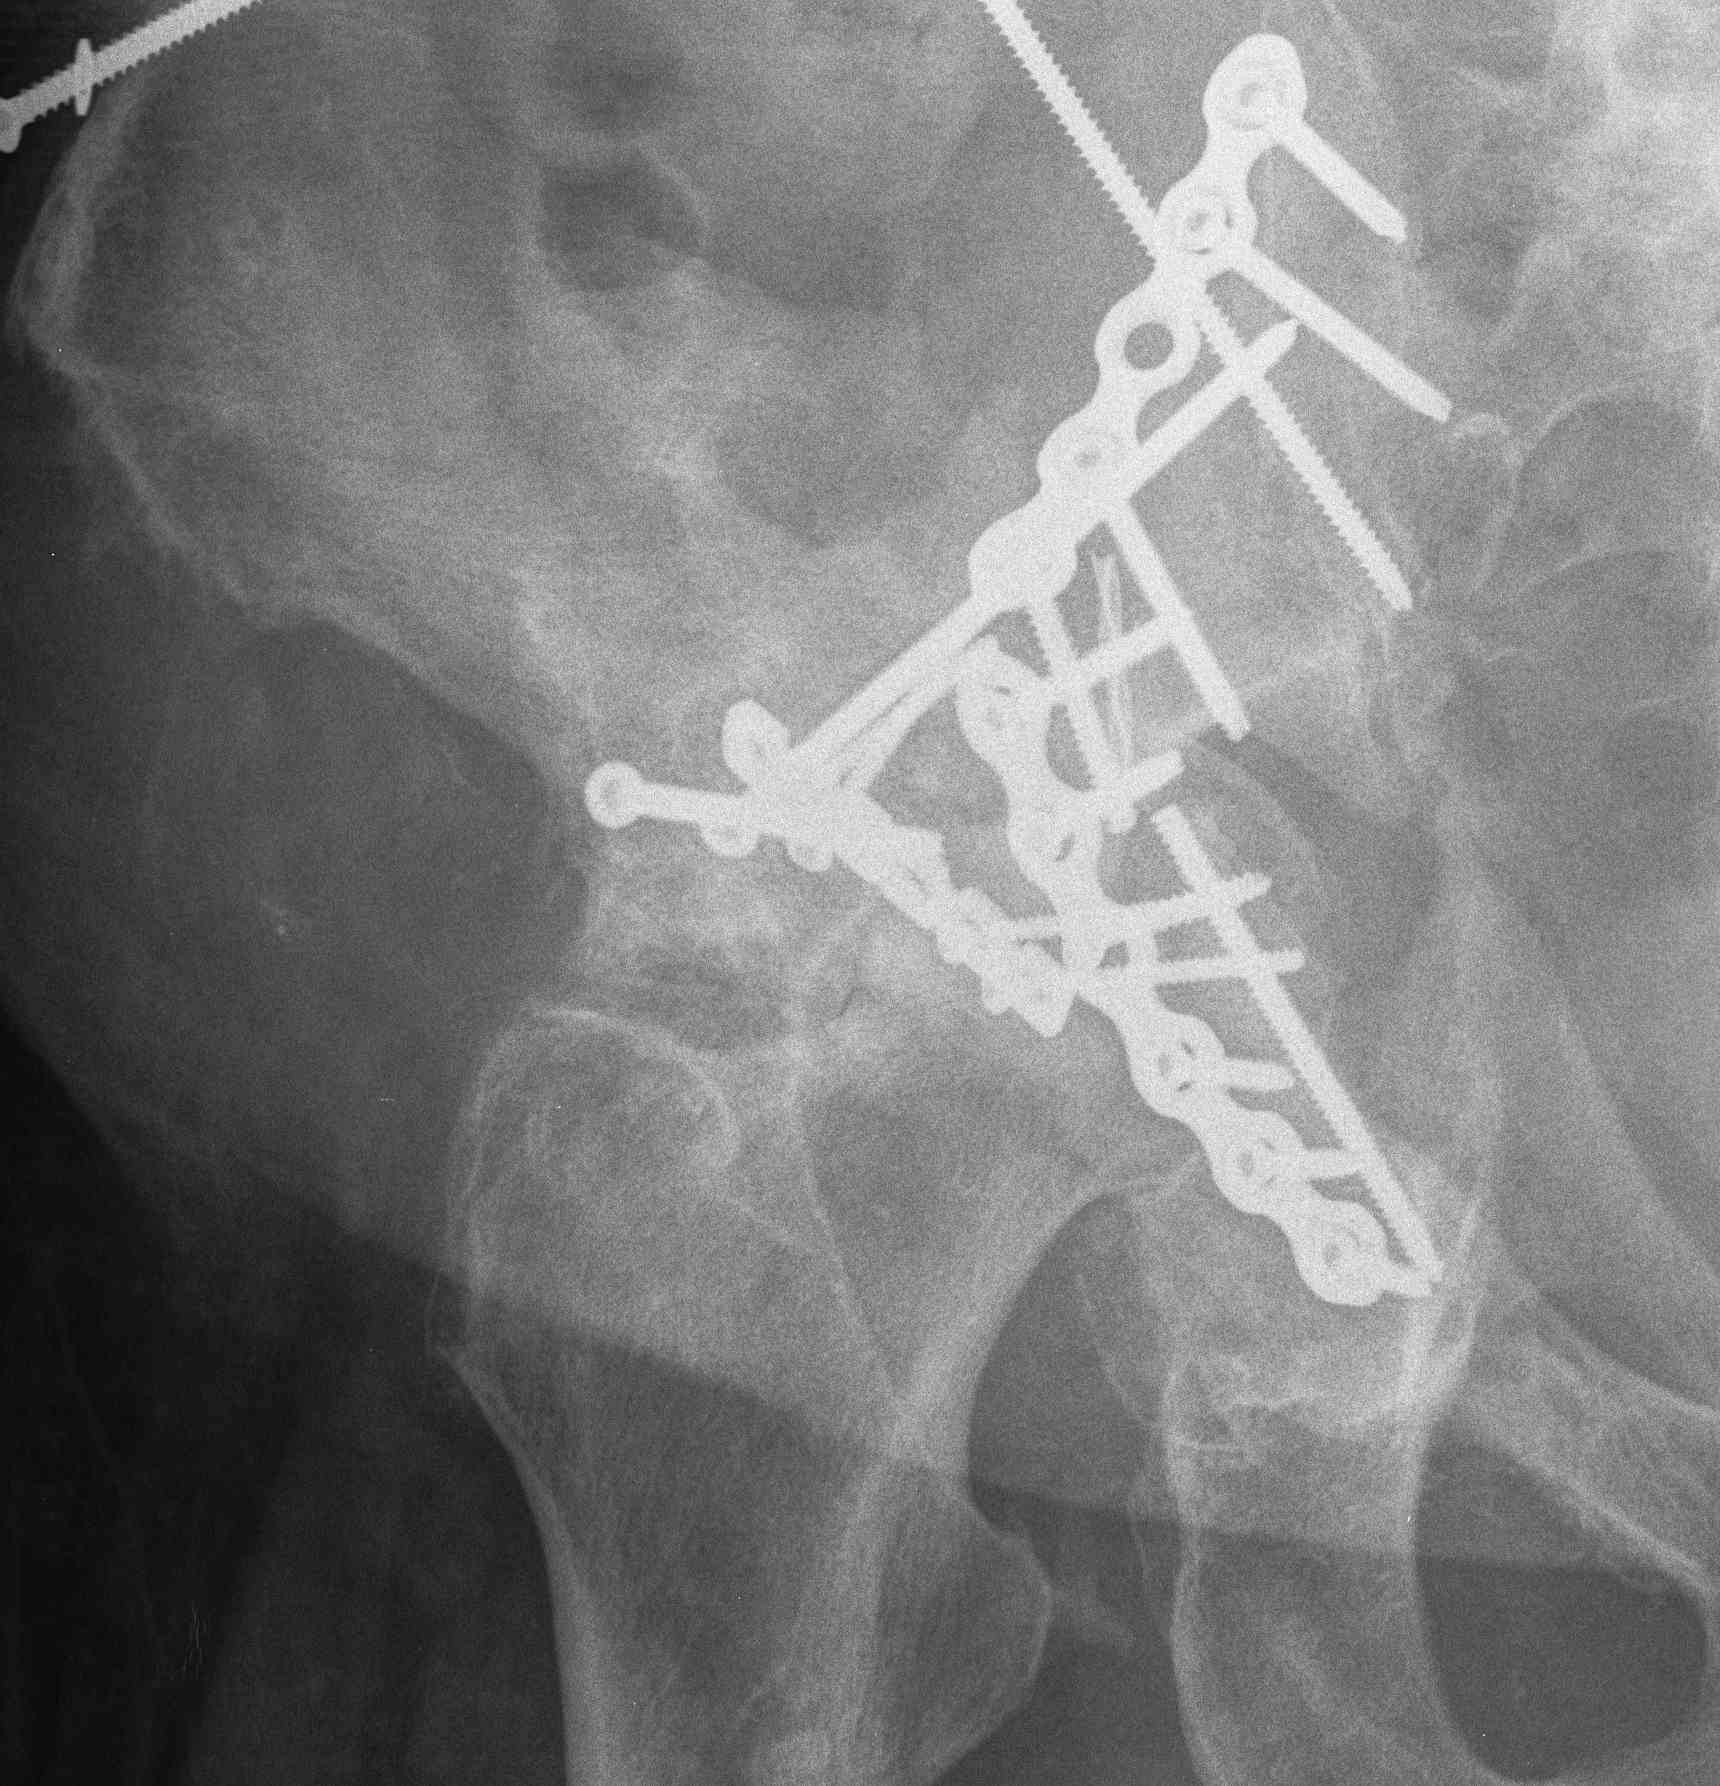

ORIF

Aim

1. Anatomic reduction

2. Provisional fixation with lag screws

3. Buttressing with curved reconstruction plates

3. Extended iliofemoral approach

- Smith-Petersen extended over iliac crest

- for transverse / both column fractures

4. Triradiate approach

- Kocher-Langenbeck with anterior extension from GT to ASIS

- wide exposure for both column fractures

- high incidence HO